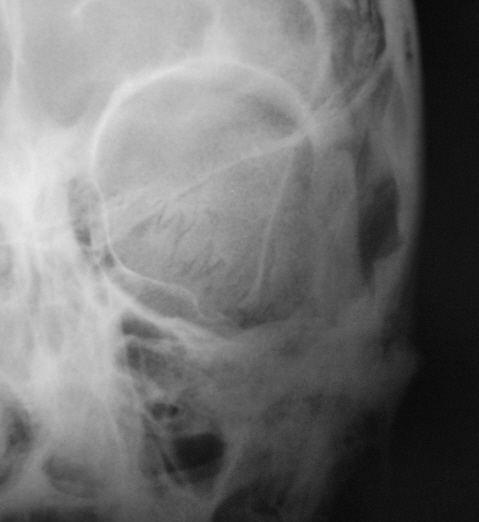

Пациент в ургентном порядке, после ДТП был доставлен в ЦРБ в ночное время. Был вызван "ургентный лаборант" для рентгенографии черепа. Пациент без сознания. С учетом состояния пациента рентгенография произведена в нестандартных проекциях - "задняя прямая".

Линейный перелом костей крыши черепа, возможно с переходом на основание. Вот только не понятно есть или нет импрессионный перелом височной кости, а ещё больше похоже на наличие пневмоцефалии.

А что скажите по поводу пирамидки и орбиты справа?

Контуры пирамиды чёткие, а вот латеральная стенка орбиты возможно сломана. Он был отправлен в ОКБ?

Линейный перелом с переходом на основание - дно средней черепной ямки. Сейчас вопрос о пирамидке и орбите не принципиальный. Главный вопрос нет ли внутричерпной гематомы. Если больной выйдет из тяжелого состояние, и встанут экспертные вопросы можно сделать Стенверс при потере слуха, Майер при кровотечении из уха. Насчет стенки орбиты - наличие перелома сомнительно, явно не видно. Также можно доснять при улучшении состояния. Судя по всему это молодой человек. Сколько лет?

Вижу только линию перелома височной и теменной костей, высока вероятность перехода на основание, остальное - домыслы и сомнения.